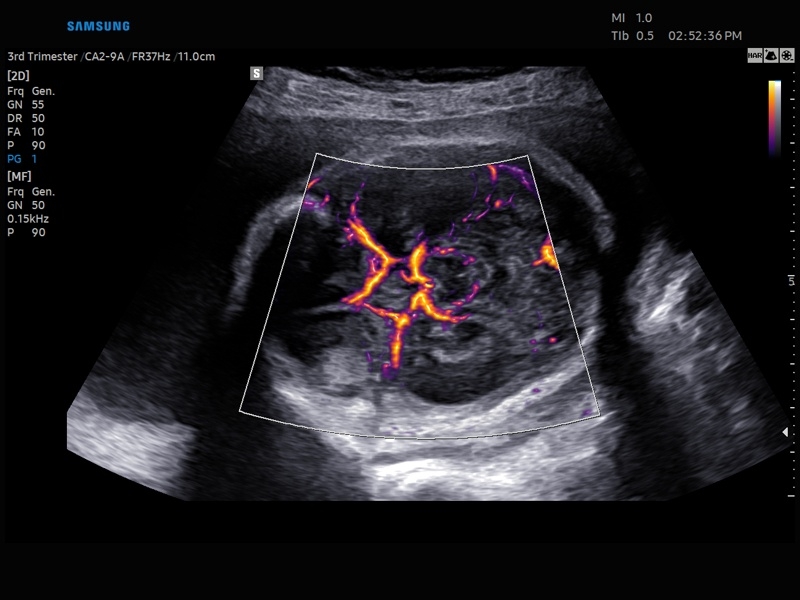

• Модуль MV-Flow – программа (режим), позволяющая визуализировать кровоток в микроциркуляторном русле с высоким разрешением без использования контраста.

• Модуль LumiFlow – программа отображения кровотока с объемной графикой для лучшего понимания архитектоники сосудистого русла.

• Модуль MV-Flow - программа (режим), позволяющая визуализировать кровоток в микроциркуляторном русле с высоким разрешением без использования контраста.